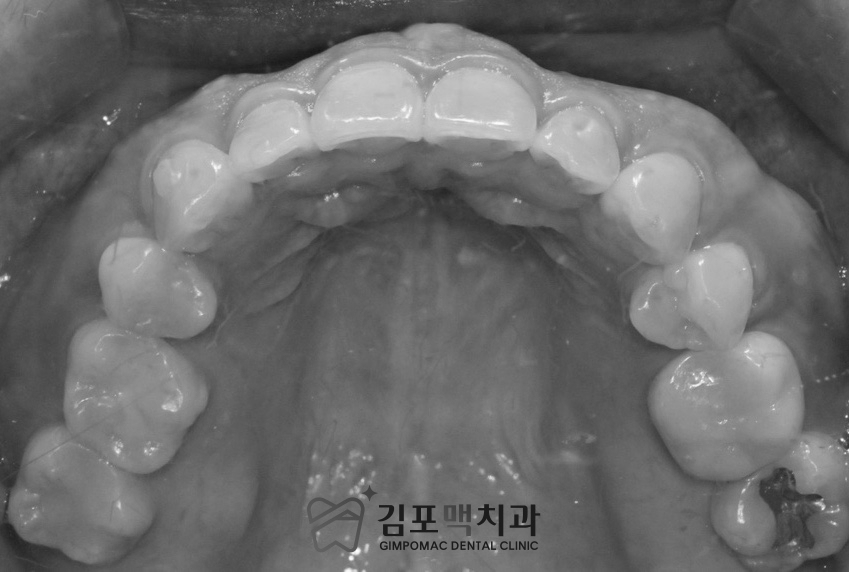

2024.06.21 촬영

다양한 각도에서의 구강 내 사진으로

정밀한 진.단과 기록을 남겼습니다.

교합면 사진도 치아의 이동을 확인할 수 있어

전체 치아가 잘 보이도록 촬영을 진행합니다.